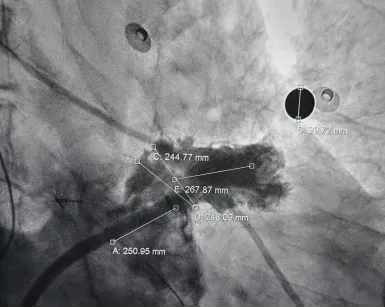

测量压缩比

右肩位下测量压缩比为10.7%

封堵合适

术前结合CT以及术中造影评估左心耳开口24.9mm,深度26.9mm,心耳内部空间合适,且患者全身情况良好,可较配合局部麻醉手术,采用极简式封堵术安全可行。术中考虑心耳开口和深度充足,可利用心耳空间进行退鞘释放封堵器,使封堵器完全封堵左心耳。术中LAFDQ-26封堵器释放时上缘未挂住梳状肌,下缘露肩,导致牵拉不稳定,选择LAFDQ-29封堵器再次尝试,封堵器展开后放置位置合适,且牵拉稳固,术后封堵器形态完整,即刻造影,未见残余漏。封堵器压缩比为10.7%,压缩合适,术中符合PASS原则,释放封堵器,术后封堵器稳固锚定在心耳壁,封堵器与心耳紧密贴合,无过度扩张风险,显著提升封堵完整性。